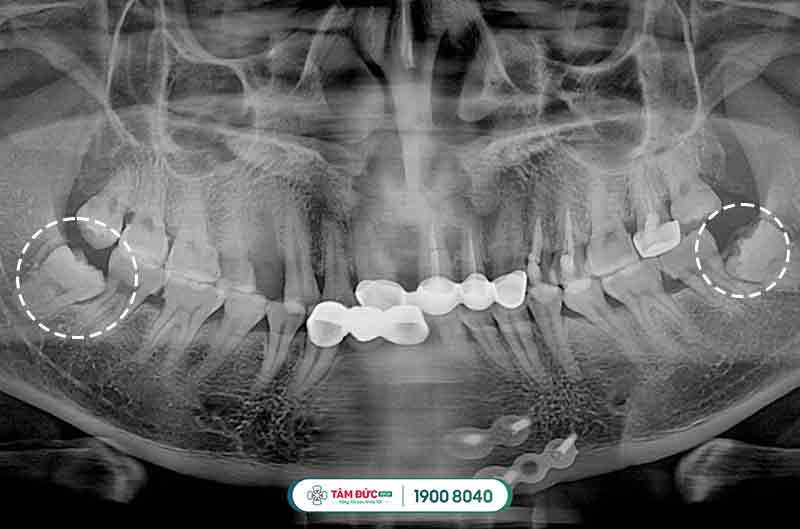

Răng khôn mọc lệch và bị sâu

Đối với các trường hợp mọc răng khôn bị thiếu chỗ vì lúc này xương hàm đã ngừng tăng trưởng và phát triển, chịu tác động bởi quá trình ăn uống hàng ngày, khiến răng khôn bị mọc ngầm dưới nướu, mọc lệch đâm vào má, vào răng bên cạnh gây nên tình trạng đau răng khôn dữ dội, khó chịu và ảnh hưởng đến cấu trúc hàm mặt, sức khỏe răng miệng.

Răng khôn mọc lệch gây đau

Răng khôn mọc lệch đâm vào răng kế cận

Răng khôn mọc ngầm thường có hiểu hiện làm nướu sưng tấy, viêm đỏ, khó há miệng. Vì xương hàm không có đủ vị trí nên nó sẽ đâm sang răng bên cạnh, nó sẽ làm chiếc răng khỏe mạnh kế bên dần bị tiêu hủy, lung lay có thể dẫn đến sâu, nặng hơn nó sẽ khiến chiếc răng này bị xô đẩy chèn ép và rụng đi gây mất răng. Răng khôn mọc lệch, ngầm thường gây ra những cơn đau răng khôn âm ỉ kéo dài trong khoản 2 tới 3 ngày.

Nhổ răng khôn không đau là một ca phẫu thuật nhỏ, không gây mê mà chỉ gây tê cục bộ tại vị trí cần nhổ giúp giảm cảm giác đau nhức cho cho chúng ta, được chỉ định cho những người có răng khôn mọc lệch, mọc ngầm, răng khôn bị tai biến, dính khớp…được thực hiện nhanh chóng dưới sự hỗ trợ của máy móc hiện đại và bác sĩ có chuyên môn cao.